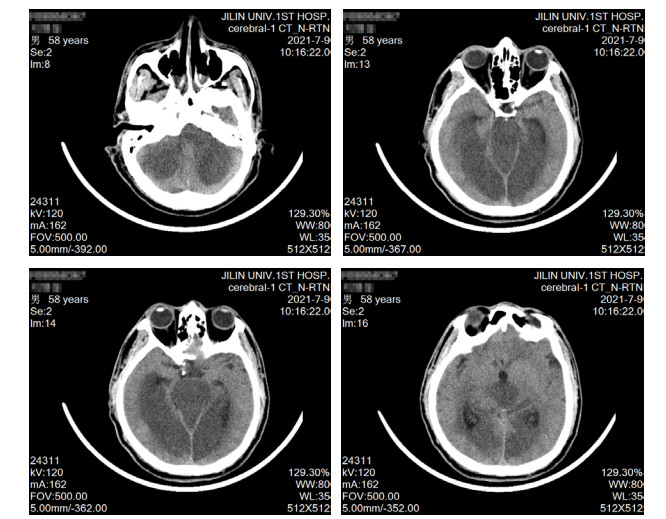

患者男性,58岁,因“头晕、黑矇3 d,意识不清15 h”于2021-07-07 18:53急诊以“意识障碍待查”收入本院重症医学科。患者3 d前无明显诱因出现头晕、黑矇,共发作7~8次,每次持续5~10 min后自行缓解,上述症状与体位无关,不伴有头痛、耳鸣、视物双影及视物旋转,无发热,曾于当地医院就诊考虑“眩晕症”,给予静点川芎嗪及血栓通后上述症状有所缓解。于入本院前15 h如厕时被家属发现倒地,呼之不应,无抽搐发作,无尿便失禁,无舌咬伤及呕吐,急由120救护车送至当地医院,测体温42.0℃(距离发病1 h),行头部及肺部CT未见明显异常,肝肾功能及降钙素原结果均正常,为求明确诊疗转诊至本院,急诊以“意识障碍待查”收入重症医学科。病程中无咳嗽、咳痰,无尿急、尿频、尿痛,无恶心、呕吐,无腹痛、腹泻。既往史情况:发现高血压病史1年,血压最高160/80 mmHg(1 mmHg=0.133 kPa),未系统诊治及监测。脑梗死病史1年。吸烟史20年,约10支/d,未戒。饮酒史20年,约100 g/d,戒酒1年余。入科查体:体温39.1℃,脉搏114次/min,呼吸23次/min,血压129/80 mmHg,外周血氧饱和度98%(鼻导管吸氧,氧流量3 L/min)。意识不清,GCS评分5分,双侧瞳孔等大同圆,直径约4.5 mm,直接、间接对光反射迟钝,皮肤、巩膜无黄染,咽部无红肿,扁桃体无肿大,气管居中,听诊双肺呼吸音清,未闻及干湿啰音。心率114次/min,律整,各瓣膜听诊区未闻及杂音及额外心音。腹软,肝脾肋下未触及,肠鸣音3~4次/min。双下肢无水肿,项强征阴性,双侧babinski征阳性,kernig征阴性,余查体不配合。辅助检查(2021-07-07,当地医院),血常规:WBC 12.3 × 109/L, NE% 67.6%,PLT 245 × 109/L,PCT 0.18 ng/mL, 肌酸激酶420 U/L,感染标志物:乙肝(−),丙肝(−),肝功能:AST 50 U/L,ALT 40 U/L, 入科诊断:意识障碍待查、发热原因待查。入科后给予降温、促醒对症治疗,约6 h后体温降至38.5℃,但患者意识无恢复,无自主咳痰能力,双肺可闻及痰鸣音,于2021-07-08给予气管插管及呼吸机辅助通气,同日出现血压下降,给予补液、升压(去甲肾上腺素)对症治疗。入科后进一步完善相关检查包括,出血热抗体:阴性,呼吸道病原核酸检测:阴性,IL-4 4.05 pg/mL,IL-6 229 pg/mL,IL-10 22.90 pg/mL,肌酸激酶13 383 Μ/L,肌红蛋白4 077 ng/mL;血栓弹力图:R 10.8 min,MA-CK 21.4 mm,K 23.4 min,综合凝血指数-19.9;肝功能:AST 2 643.0 M/L,ALT 2 711.9 M/L,ALB 32.1 g/L,TB 142.5 μmmol/L,DB 85.1 μmmol/L,CB 57.4 μmmol/L;肾功能:Scr 94.3 μmol/L、BMN 7.1 mmol/L;血常规及凝血相关指标变化见表 1;头部CT提示双侧小脑半球、脑干、双侧枕叶、丘脑、放射冠、半卵圆中心低密度影(图 1);肺部CT提示支气管炎、双肺散在炎症、胸主动脉及冠脉动脉硬化(图 2)。综合病史、体征和辅助检查明确临床诊断为:椎基底动脉脑梗死、中枢性高热、多器官功能障碍综合征(循环、肝脏、血液)、横纹肌溶解综合征,给予脱水降颅压、营养神经、促醒、纠正凝血异常对症治疗,患者病情无好转,于2021-07-09家属放弃治疗,出院后死亡。

图 1 2021-07-09患者头部CT

本病例入院前有头晕、黑曚后循环缺血症状,经改善循环对症治疗后有所缓解,但本次以突发的意识障碍入院,查体双侧babinski征阳性,结合头部CT可诊断为由基底动脉闭塞所致的后循环脑梗死,其影像学特点符合基底动脉尖综合征[9]。所谓基底动脉尖综合征(top of basilar syndrome, TOBS)是指基底动脉分支包括大脑后动脉和小脑上动脉的闭塞导致的综合征,其供血区包括中脑、丘脑、小脑上部、颞叶内侧和枕叶,临床表现为意识障碍、中枢性高热。本病例高热发生在意识障碍后1 h,不符合经典型热射病的时间特点,同时该患生活在中国东北吉林省,气温在24℃左右,无剧烈活动的诱因,不符合劳力型热射病定义的范畴[10]。此外,患者不伴有感染相关临床症状,以及细菌感染血清标志物降钙素原正常,痰、血、尿培养结果阴性等均不支持感染性发热。因此,其高热原因应考虑为基底动脉闭塞导致下丘脑体温调节中枢受损所致中枢性高热。通常脑血管病合并中枢性高热最常见于脑出血,少数也可见于大面积脑梗死或脑干梗死,其中大面积脑梗死可造成脑水肿刺激与压迫体温中枢或影响其下行传导通路[6, 8, 11]